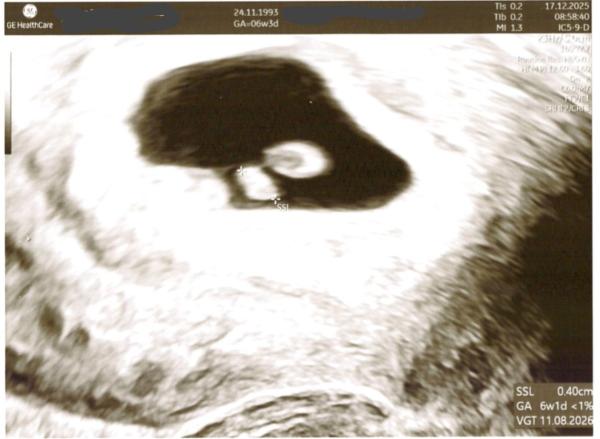

Hallöchen, Heute war bei 6+3 mein erster FA-Termin, wurde aber aufgrund meiner Zykluslänge von 30 Tagen auf 6+1 zurückdatiert, passt auch super zur Größe des kleinen Mitbewohners (0,40 cm). Herzaktivität konnte man zum Glück auch erkennen. Wie sind eure ersten FA-Termine so gelaufen?